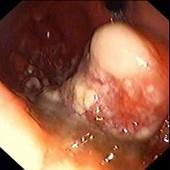

问题 患者,女,19岁,反复发热、上腹痛、消瘦1月,查体:上腹部饱满,余无阳性体征。电子胃镜图片如下,诊断为 ( )

选项 A.胃癌 B.胃淋巴瘤 C.胃溃疡 D.胃溃疡并真菌感染 E.胃多发性息肉

答案 B